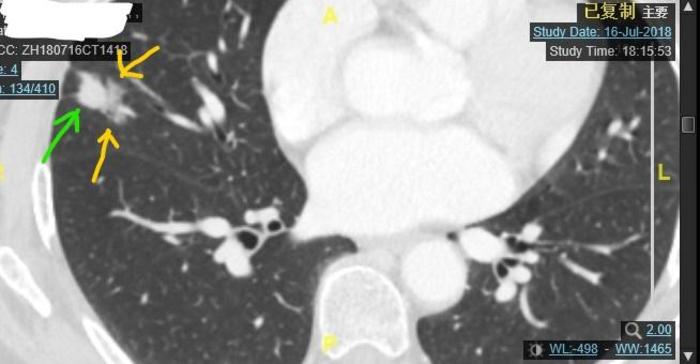

病例6,实性成分内侧部分磨玻璃成分

绿色箭头指示的是混合磨玻璃结节的实性成分,这个结节以实性成分为主。结节的内侧三分之一由磨玻璃成分构成,用两个黄色箭头指示。这个结节最大径23毫米。病理如下图:

这个实性成分为主的混合磨玻璃结节是浸润性腺癌,以腺泡型为主。所以结节恶性度比较低。Ki-76才2%,说明肿瘤生长很很慢。对Ki-76意义不懂的话,可以点击参考我的一篇健康号文章链接:肺癌肺结节病理报告上的KI-67是什么意思?。